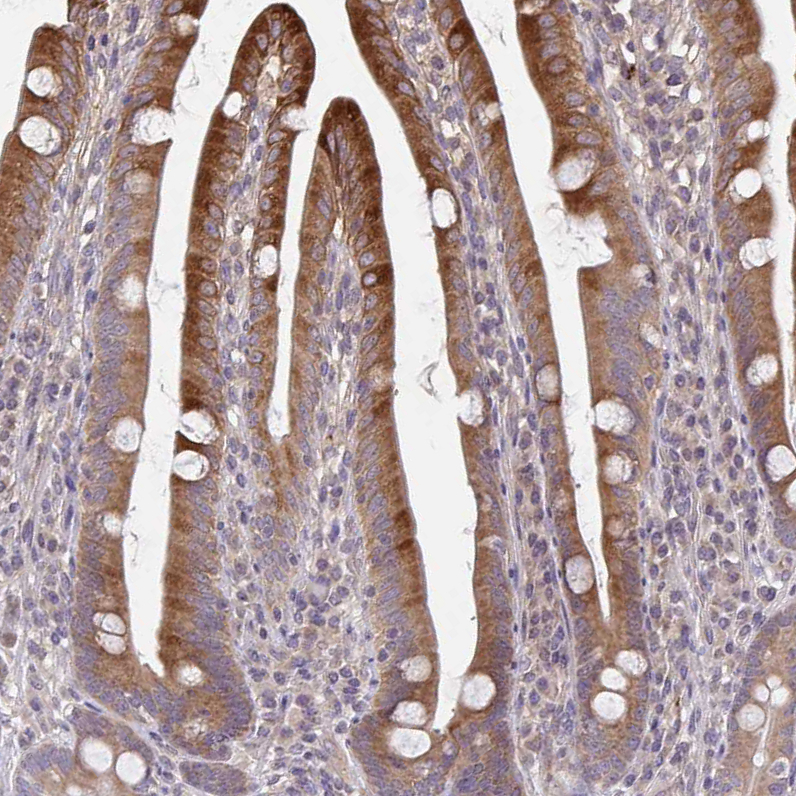

Immunohistochemical staining of human duodenum shows moderate cytoplasmic positivity in glandular cells.